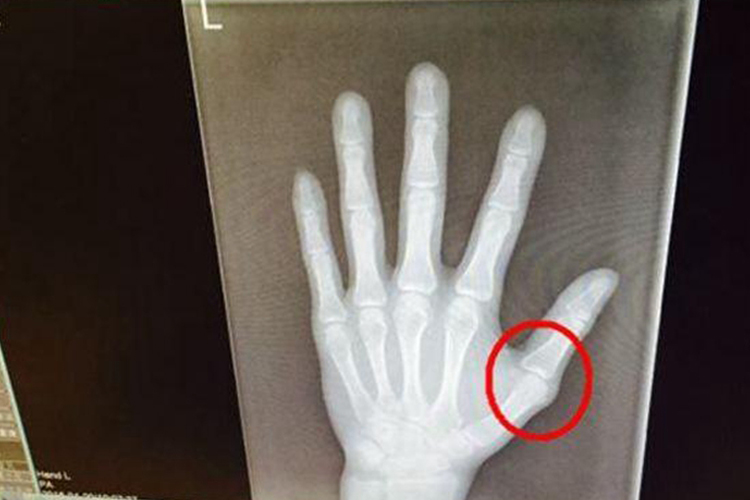

骨头错位的恢复时间主要取决于错位的具体类型是骨折引起的错位还是关节脱位,以及错位的严重程度和治疗方式,一般是2周到12个月不等。

1、骨折错位:

- 轻微错位:如果骨折端的错位不明显,通过保守治疗如手法复位和外部固定(石膏或夹板),恢复时间通常在4-6周。

- 严重错位:需要更复杂的治疗,可能包括手术复位和内固定。这种情况下,临床愈合可能需要3个月左右,而功能恢复可能需要8-12个月。